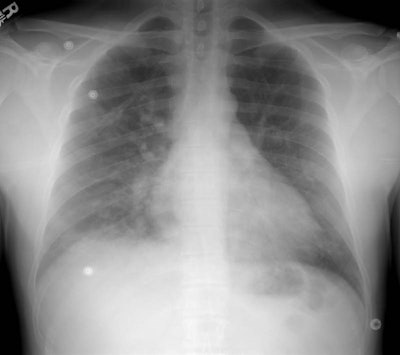

High Altitude Pulmonary Edema:

The patient shown below was an Intern who presented with shortness of breath after climbing Mount Rainer. The portable CXR revealed patchy alveolar airspace abnormalities predominantly confined to the mid and lower lung zones.